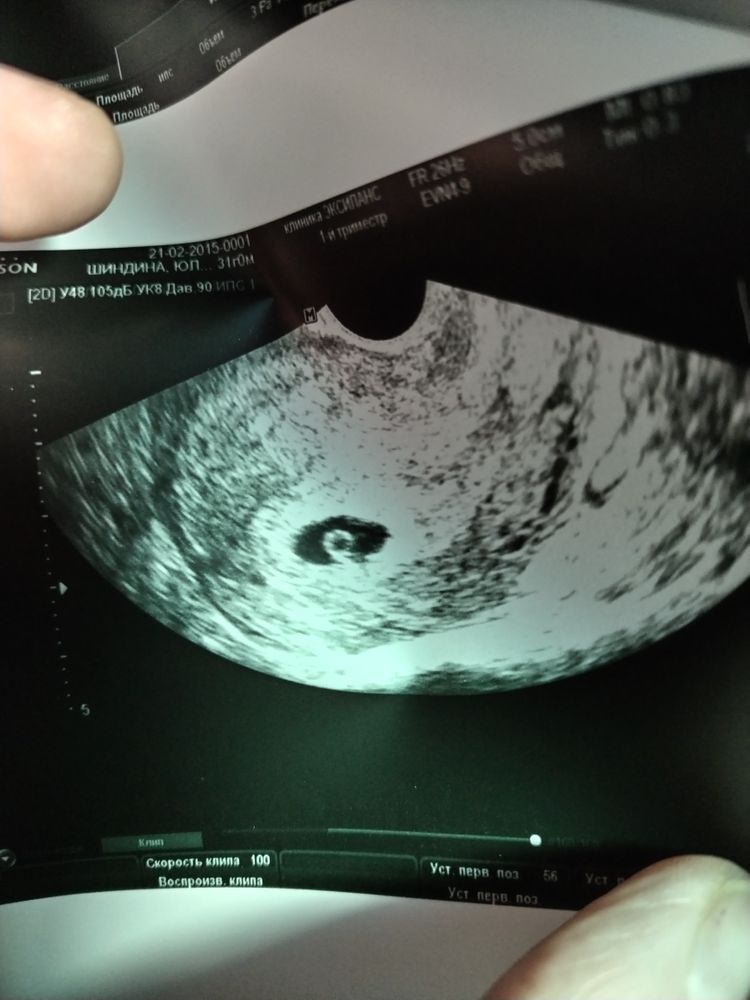

Изображение Вот нашла фото своей,, креветки,, 7 недель ровно. Сейчас 7 лет уже) Юлия,

23.03.2023